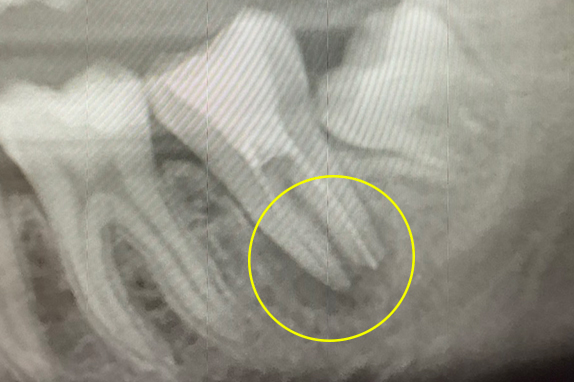

CASE 02 マイクロエンド(精密根管治療)+歯周基本治療

-

- 主訴

- 右も左も痛くて噛めない(60代女性)

-

- 回数期間

- 15回 約6ヶ月

-

- 治療法

- マイクロエンド(精密根管治療)+歯周基本治療

-

- 治療費用

- 約60万円(税抜)

右も左も痛くて噛めないという主訴で来院。マイクロエンドをし歯周基本治療で改善したケースです。

<リスク・副作用>

治療後は痛み、腫れ、痺れなどの副作用が生じる場合があります。症状が再発する可能性があります。